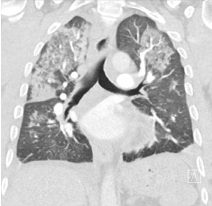

A 49-year-old male with no prior comorbidities presented to the emergency room (ER) with a 7-day history of fever, cough and shortness of breath. On admission, the patient had a blood pressure of 80/56 mmHg, a heart rate of 120 bpm, a respiratory rate of 36/minute, elevated jugular venous pressure, clear lung fields and muffled heart sounds on auscultation. An electrocardiogram was done, which showed sinus tachycardia with low-voltage QRS complexes. A screening bedside echocardiogram showed a large pericardial effusion (maximum thickness of 28 mm) with right ventricular diastolic collapse, suggestive of tamponade physiology. A bedside echocardiography-guided pericardiocentesis was attempted in the ER. Initially, 15 ml of haemorrhagic fluid was drained, after which no further fluid was drained. Cardiology consultation was obtained, and the patient was transferred to the cardiac catheterization laboratory.

Fluoroscopy was done, and the sheath was found to be in the splenic capsule (Figure 1). Under fluoroscopic guidance, a pigtail was inserted over a 0.035” J-tipped Terumo wire, after confirming the position of the wire in the pericardial space (Figure 2), and 250 ml of pericardial fluid was drained. Post-pericardiocentesis, the patient was vitally stable.